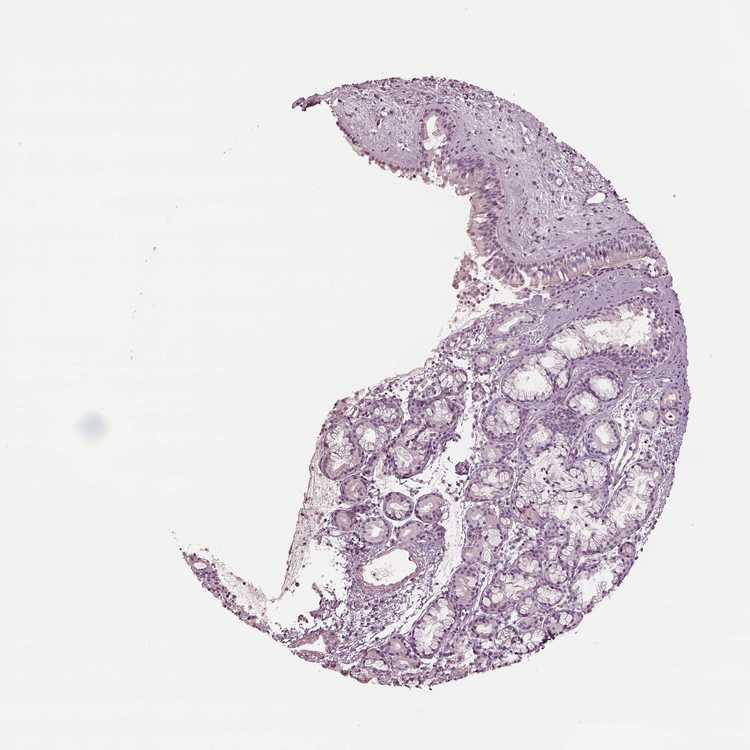

NASOPHARYNX - Antibody stainingi

Antibody staining in the annotated cell types in the current human tissue is reported as not detected, low, medium, or high, based on conventional immunohistochemistry profiling in selected tissues. This score is based on the combination of the staining intensity and fraction of stained cells.

Each image is clickable and will lead to virtual microscopy that enables deeper exploration of all samples and also displays staining intensity scores, fraction scores and subcellular localization as well as patient and tissue information for each sample.

Antibody HPA061969

Respiratory epithelial cells Not detected